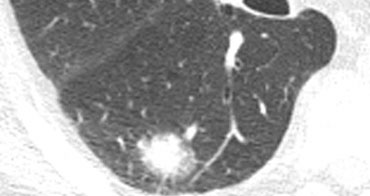

Baseline scan and scans after contrast enhancement. Benign lesion with Baseline scan and scans after contrast enhancement. Benign lesion with

Contrast enhancement

Contrast enhancement less than 15 HU has a very high predictive value for benignity (99%).

After a baseline scan, 4 consecutive scans at 1 minute interval are performed.

This applies only for nodules with the following selection criteria:

1. Nodule > 5mm

2. Relatively spherical

3. Homogeneous, no necrosis, fat or calcification

4. No motion or beam hardening artifacts